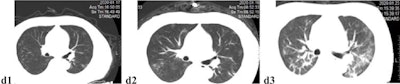

Unenhanced axial CT images of a 52-year-old male doctor with asthma and exposure to patients with confirmed SARS-CoV-2 infection, initially presenting with fever, nonproductive cough, dyspnea, and myalgia, who rapidly progressed to a severe form requiring mechanical ventilation. (D1) Multifocal, limited ground-glass opacity in the periphery of both lungs, predominantly affecting left lung. (D2) Two days later, focal ground-glass opacity has increased in size and density, and new diffuse ill-defined ground-glass opacity has developed. (D3) After four days of mask oxygen supplementation, disease progressed further, with more patchy consolidations and linear densities observed in nearly all lung zones except the anterior part of both lungs. Images courtesy of European Radiology.